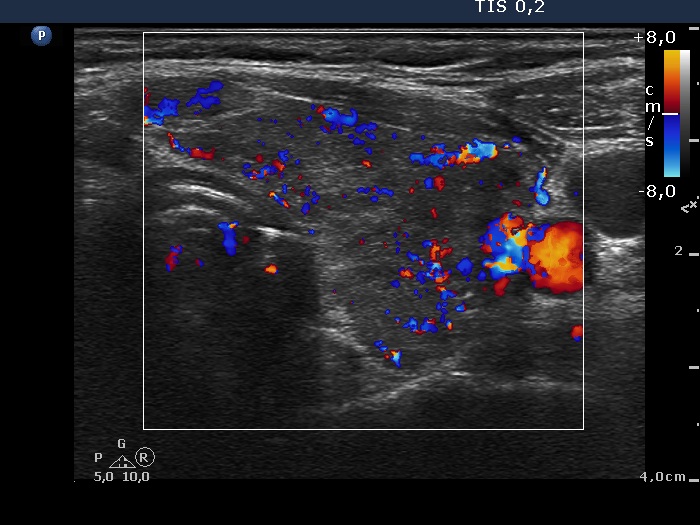

Consecutively operated patients with autoimmune thyroid disease - case 55 (1184) (ultrasonographic picture 6)

Left lobe, transverse view, color Doppler mode. The vascularization is a bit increased.